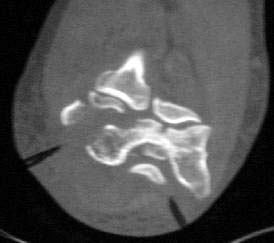

Images are of 59 yo female with low, comminuted distal humerus fx with fragments free posteriorly, high degree of comminution laterally plus involvement of the medial condyle.

Any thoughts re: management are appreciated. Approach to allow access and fixation medially as well as anterior & posterior. Total elbow arthroplasty ?